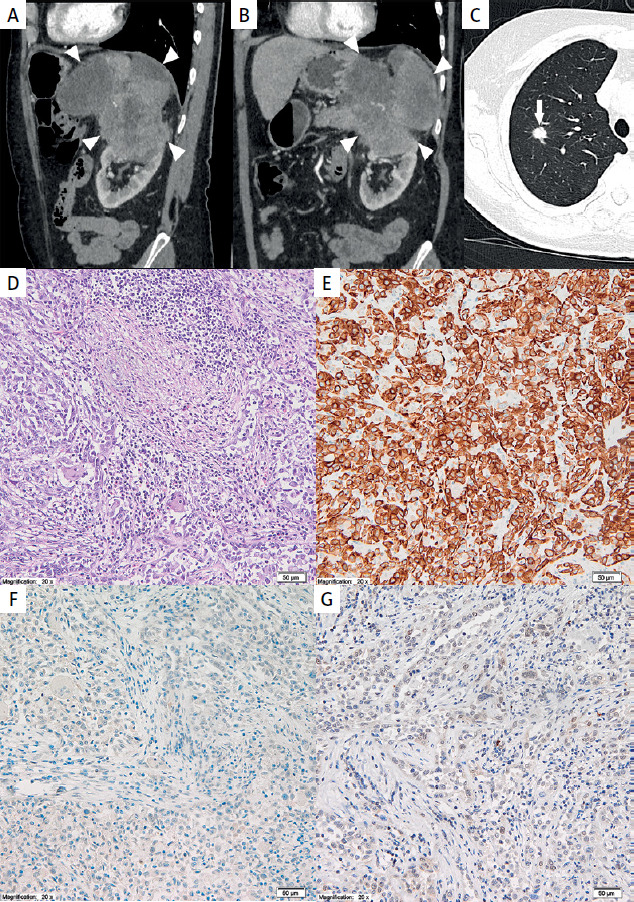

Rare presentation of pancreatic carcinoma mimicking advanced renal cell carcinoma.